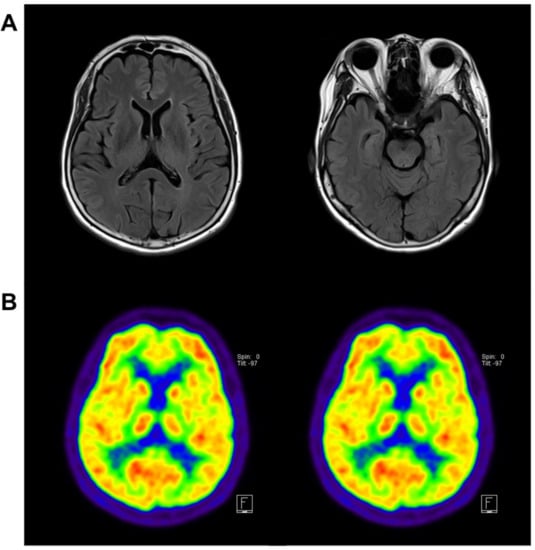

4.1. Patient Information